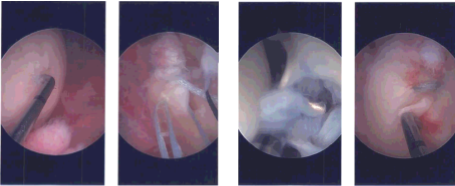

The left knee was prepped and draped aseptically in a usual fashion. Preop antibiotic was given. The limb was exsanguinated and the tourniquet was elevated. A lateral entry portal was made with the use of a knife. An arthroscope was inserted. Examination of the patellofemoral compartment showed intact cartilage.

The medial entry portal was made with the use of spinal needle under visualization. Examination of the medial compartment showed medial meniscus root tear, which was hanging over the flimsy tissue to the capsule, which could easily be freed. Decision was done to medial meniscus root repair.

Arthrex medial meniscus root repair was used and was inserted (3:18) with incision was given on the tibia (3:20) was inserted. A FlipCutter was inserted through the (3:23) and was brought out to the posterior tibial plateau in the region of the meniscus root.

The FlipCutter was flipped so as to ream to about 5 mm to make a trough for the root. A wire was used to keep the canal patent. Now, FiberLink x2 were passed through the root with the use of labral scorpion. They were passed down through the tunnel and brought out onto the tibia. Root was found to be in a good position onto the bone.

The sutures were tied onto each other over a button. After the repair of the suture, it was found that the roots were not opposed to the bone, so a decision was made to put 4.75 SwiveLock, which was inserted after preparing the hole with a sutures passed through it. A good reduction and repair of the medial meniscus was achieved.

Examination of the intercondylar notch showed intact ACL. Examination of the lateral compartment showed partial tearing of the lateral meniscus, which was debrided with the use of shaver. Final pictures were taken and saved.

Intraoperative Arthroscopy Images